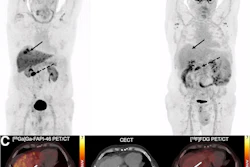

Complete response to immune checkpoint inhibitor therapy on Ga-68 PSMA-PET/CT. Maximum intensity projection (MIP) images from an 83-year-old male with metastatic HCC treated with atezolizumab and bevacizumab. (A) Baseline pretreatment image demonstrates a large, intensely PSMA-avid lesion in the right hepatic lobe, along with multiple metastatic lesions throughout the abdomen and skeleton. (B) Follow-up scan performed four months after initiating therapy shows complete resolution of PSMA uptake in all hepatic and extrahepatic disease.European Journal of Nuclear Medicine and Molecular Imaging